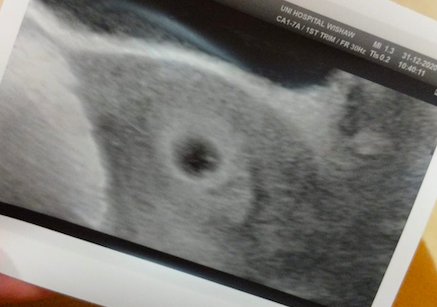

Had the scan today to rule out ectopic and all looks great.

They said they can see a fetal pole and yolk sac. (I dunno if my eyes are that good, haha)

Measuring where I should be, HCG levels are great! Feels like a relief but I'm still nervous because it's so early. Wish I could fast forward a few weeks.